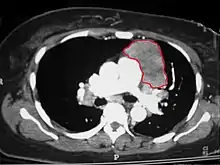

CT scan of the chest revealing a large necrotic mass in the left anterior mediastinum (indicated by the red line). Histology later established the diagnosis of a thymoma.

When a thymoma is suspected, a CT/CAT scan is generally performed to estimate the size and extent of the tumor, and the lesion is sampled with a CT-guided needle biopsy. Increased vascular enhancement on CT scans can be indicative of malignancy, as can be pleural deposits.[3] Limited biopsies are associated with a very small risk of pneumomediastinum or mediastinitis and an even-lower risk of damaging the heart or large blood vessels. Sometimes thymoma metastasize for instance to the abdomen.[5]